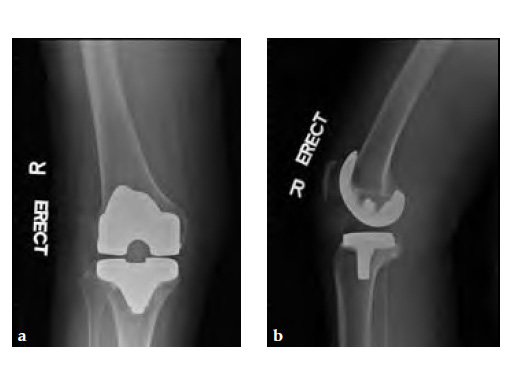

Case 2: A 76-year-old female underwent right total knee replacement 5 years ago and left total knee replacement 4.5 years ago

The patient underwent left L5S1 minimally invasive TLIF with pedicle screws 2 years ago for left lumbar 5th radiculopathy. At the same time she was put on fosamax for osteoporosis.

Case provided by Merng Koon Wong, Singapore, Singapore

Based on the negative MRI thigh and positive MRI lumbar spine of multiple levels of spinal stenosis, the patient underwent epidural analgesic injection. Patient sustained right femur midshaft periprosthetic fracture the next day after her epidural injection with no trauma.

Patient was allowed and achieved immediate weight bearing and in 6 weeks callus is seen at the fracture site (see Fig 7a-b).